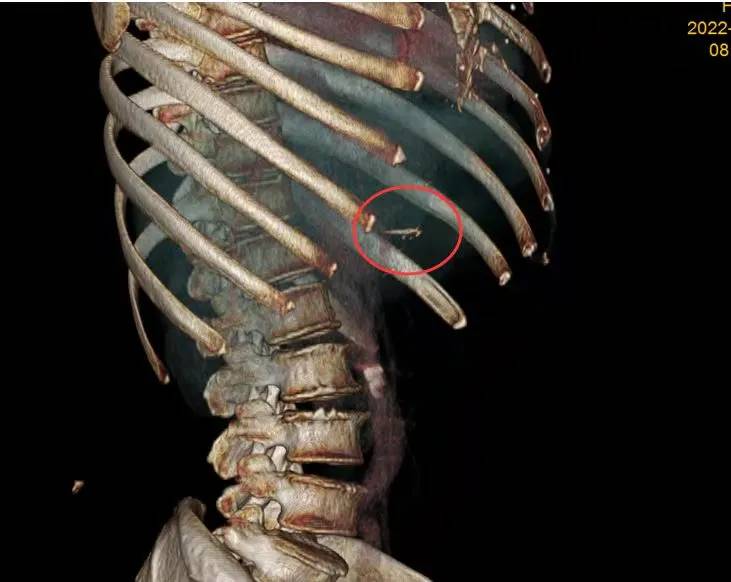

▲影像图片中鱼刺清晰可见。

据医生介绍,在手术中看到,鱼刺连通胃壁和肝左外叶,取出的鱼刺长2.1厘米。手术用时约两个小时,过程比较顺利。手术后,该女子经过7天的治疗观察后顺利出院。